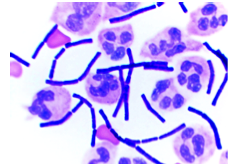

What organism?

B. anthrax

(notice BoX car appearance)